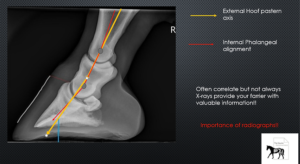

The Truth about Hoof Pastern Axis

There is conflicting rhetoric traversing the social universe about the importance and ideals of phalangeal alignment and stance angles, concepts … Continue reading The Truth about Hoof Pastern Axis